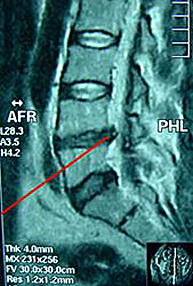

Hernia discal lumbar Centro M dico Teknon Very well made.

Protusi n y hernia Cu l es la diferencia Very well made.

Rotura Protusi n y Hernia Discal InfoEspalda Very well made.

Tratamiento para Ruptura de Anillo Fibroso Clinica de Columna CDMX Very well made.